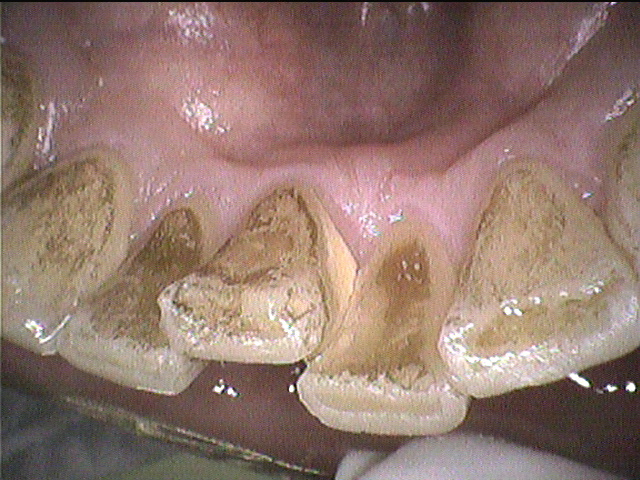

クリーニング前

磨き残しは少なく、フロスもしっかり使われていて

プラークコントロールはとても良好なのですが、

歯石やタバコによるステインがつきやすく

何度か定期的にクリーニングに来てくださっている患者さんです。

歯石やステインをできる範囲で除去しました。